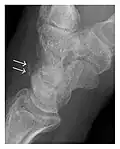

Occult osseous injuries may result from a direct blow to the bone by compressive forces of adjacent bones against one another or by traction forces during an avulsion injury. Lesions in the tibial plateau, hip, ankle, and wrist are often missed. In a tibial plateau fracture, any disruption of the posterior and anterior cortical rims of the plateau should be sought. Impaction of subchondral bone will appear as an increased sclerosis of the subchondral bone (Figure 1). In the hip, posterior acetabular fractures also present subtle radiographic findings. The acetabular lines should then be carefully examined keeping in mind that the posterior rim, which is harder to see on X-rays, is more frequently fractured than the anterior rim (Figure 2). In the wrist, detection of carpal bone fractures is often challenging, with up to 18% of scaphoid fractures radiographically occult. Carpal fractures, especially the scaphoid, are associated with the risk of avascular necrosis. In apparently normal wrist radiographs from symptomatic patients, if there is history of a fall on an outstretched hand with pain in the anatomic snuffbox, suggesting scaphoid injury, the initial examination with posteroanterior, lateral, and pronation oblique views must be complemented by other specific views such as supination oblique and the "scaphoid" view A careful examination of cortices for evidence of discontinuity or offset and cancellous bone for lucency is necessary (Figure 3).[1]

Figure 3: A 26-year-old man presenting with wrist pain after being assaulted. (a) Initial anteroposterior radiograph shows a subtle linear lucency within the scaphoid extending to the scaphocapitate articular surface that was overlooked (arrow). (b) Initial "scaphoid" view was negative. (c) Followup anteroposterior radiographs, 12 days later, shows obvious scaphoid fracture (arrows).[1]

Triquetral fracture usually occurs on the dorsal aspect by impingement from the ulnar styloid or avulsion of strong ligamentous attachment. The dorsal avulsion fracture or "chip fracture" appears as a small bony fragment on the dorsal aspect of the triquetrum and is best detected on the lateral view(Figure 4). When radiography is negative in patients with high suspicion of a fracture, both MRI and MDCT will be of value. However, it has been shown that MRI is superior for detecting trabecular fractures in carpal bones.